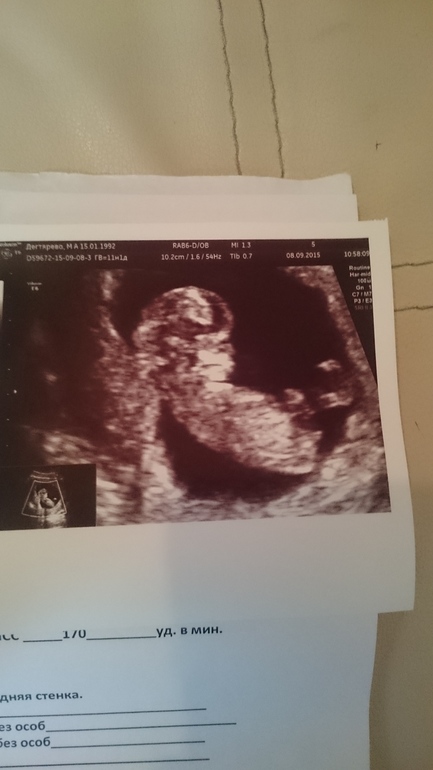

Ура! 1-скрининг

УЗИ, КТГ, доплерДевочки ну вот и я там побывала)))) врач молчун! Кто что сможет расшифруйте) ну и вдруг пол видно а я в этом не понимаю тоже скажите пожалуйста))

Поздравляю вас!А нам завтра предстоит :)Кстати, по поводу пола, у вас ЧСС 170 уд/мин, скорее всего девочка, не знаю насколько правда определять пол по сердцебиению, но многие говорят достоверность 88%)